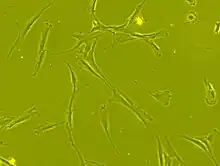

Cellule mésenchymateuse

Les CSM ont un corps cellulaire petit, avec quelques éléments cellulaires longs et minces.

Ce corps cellulaire contient un gros noyau rond avec un nucléole proéminent, entouré de fines particules de chromatine dispersées, donnant au noyau une apparence claire.

Le reste du corps cellulaire contient une petite quantité d'appareils de Golgi, un réticulum endoplasmique rugueux, des mitochondries et des polyribosomes.

Ces cellules, longues et minces, sont largement dispersées, et la matrice extracellulaire adjacente est peuplée de quelques fibrilles réticulaires mais dépourvue d’autre types de fibrilles de collagène[39],[36].